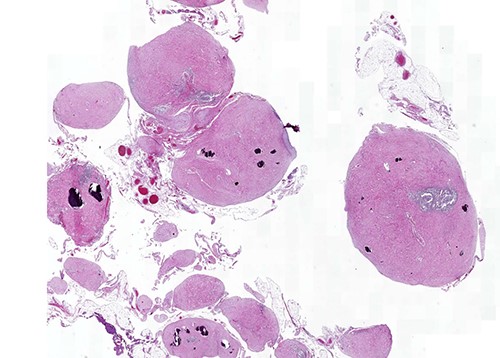

On macroscopic examination, numerous (>100) gray-white-colored grape-like hard nodules were seen, with the largest measuring 4 cm and the smallest measuring 0.2 cm. They were well-circumscribed, unencapsulated, spherical or lobulated and cut surfaces were homogenous, gray-white and firm to rubbery. Microscopically, hypocellular spindle cell proliferations embedded in abundant hyalinized collagen were seen, occasionally dystrophic or psammomatous calcifications interspersed with sparse lymphoplasmacytic infiltrate that may form lymphoid follicles. There was no mitosis, atypia or necrosis (Figs 2 and 3).

Calcifying fibrous tumor with abundant paucicellular hyalinized collagen, interspersed psammomatous or dystrophic calcifications and inflammatory infiltrate consisting of lymphocytes and plasmocytes (H&E, ×4).